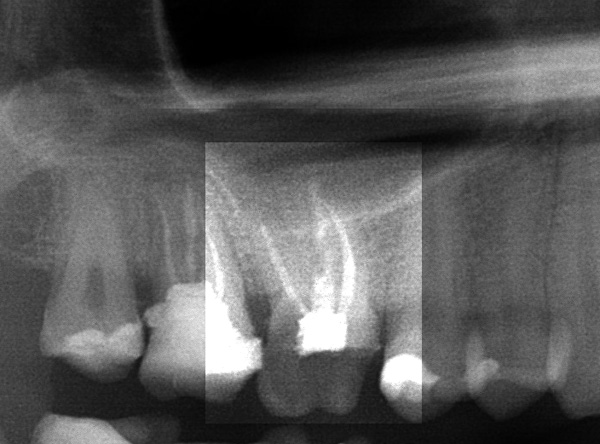

Das Ausgangsröntgenbild zeigt inhomogene und zu kurze Wurzelkanalfüllungen:

Wir haben alle Wurzelkanäle gereinigt, desinfiziert und vollständig gefüllt: